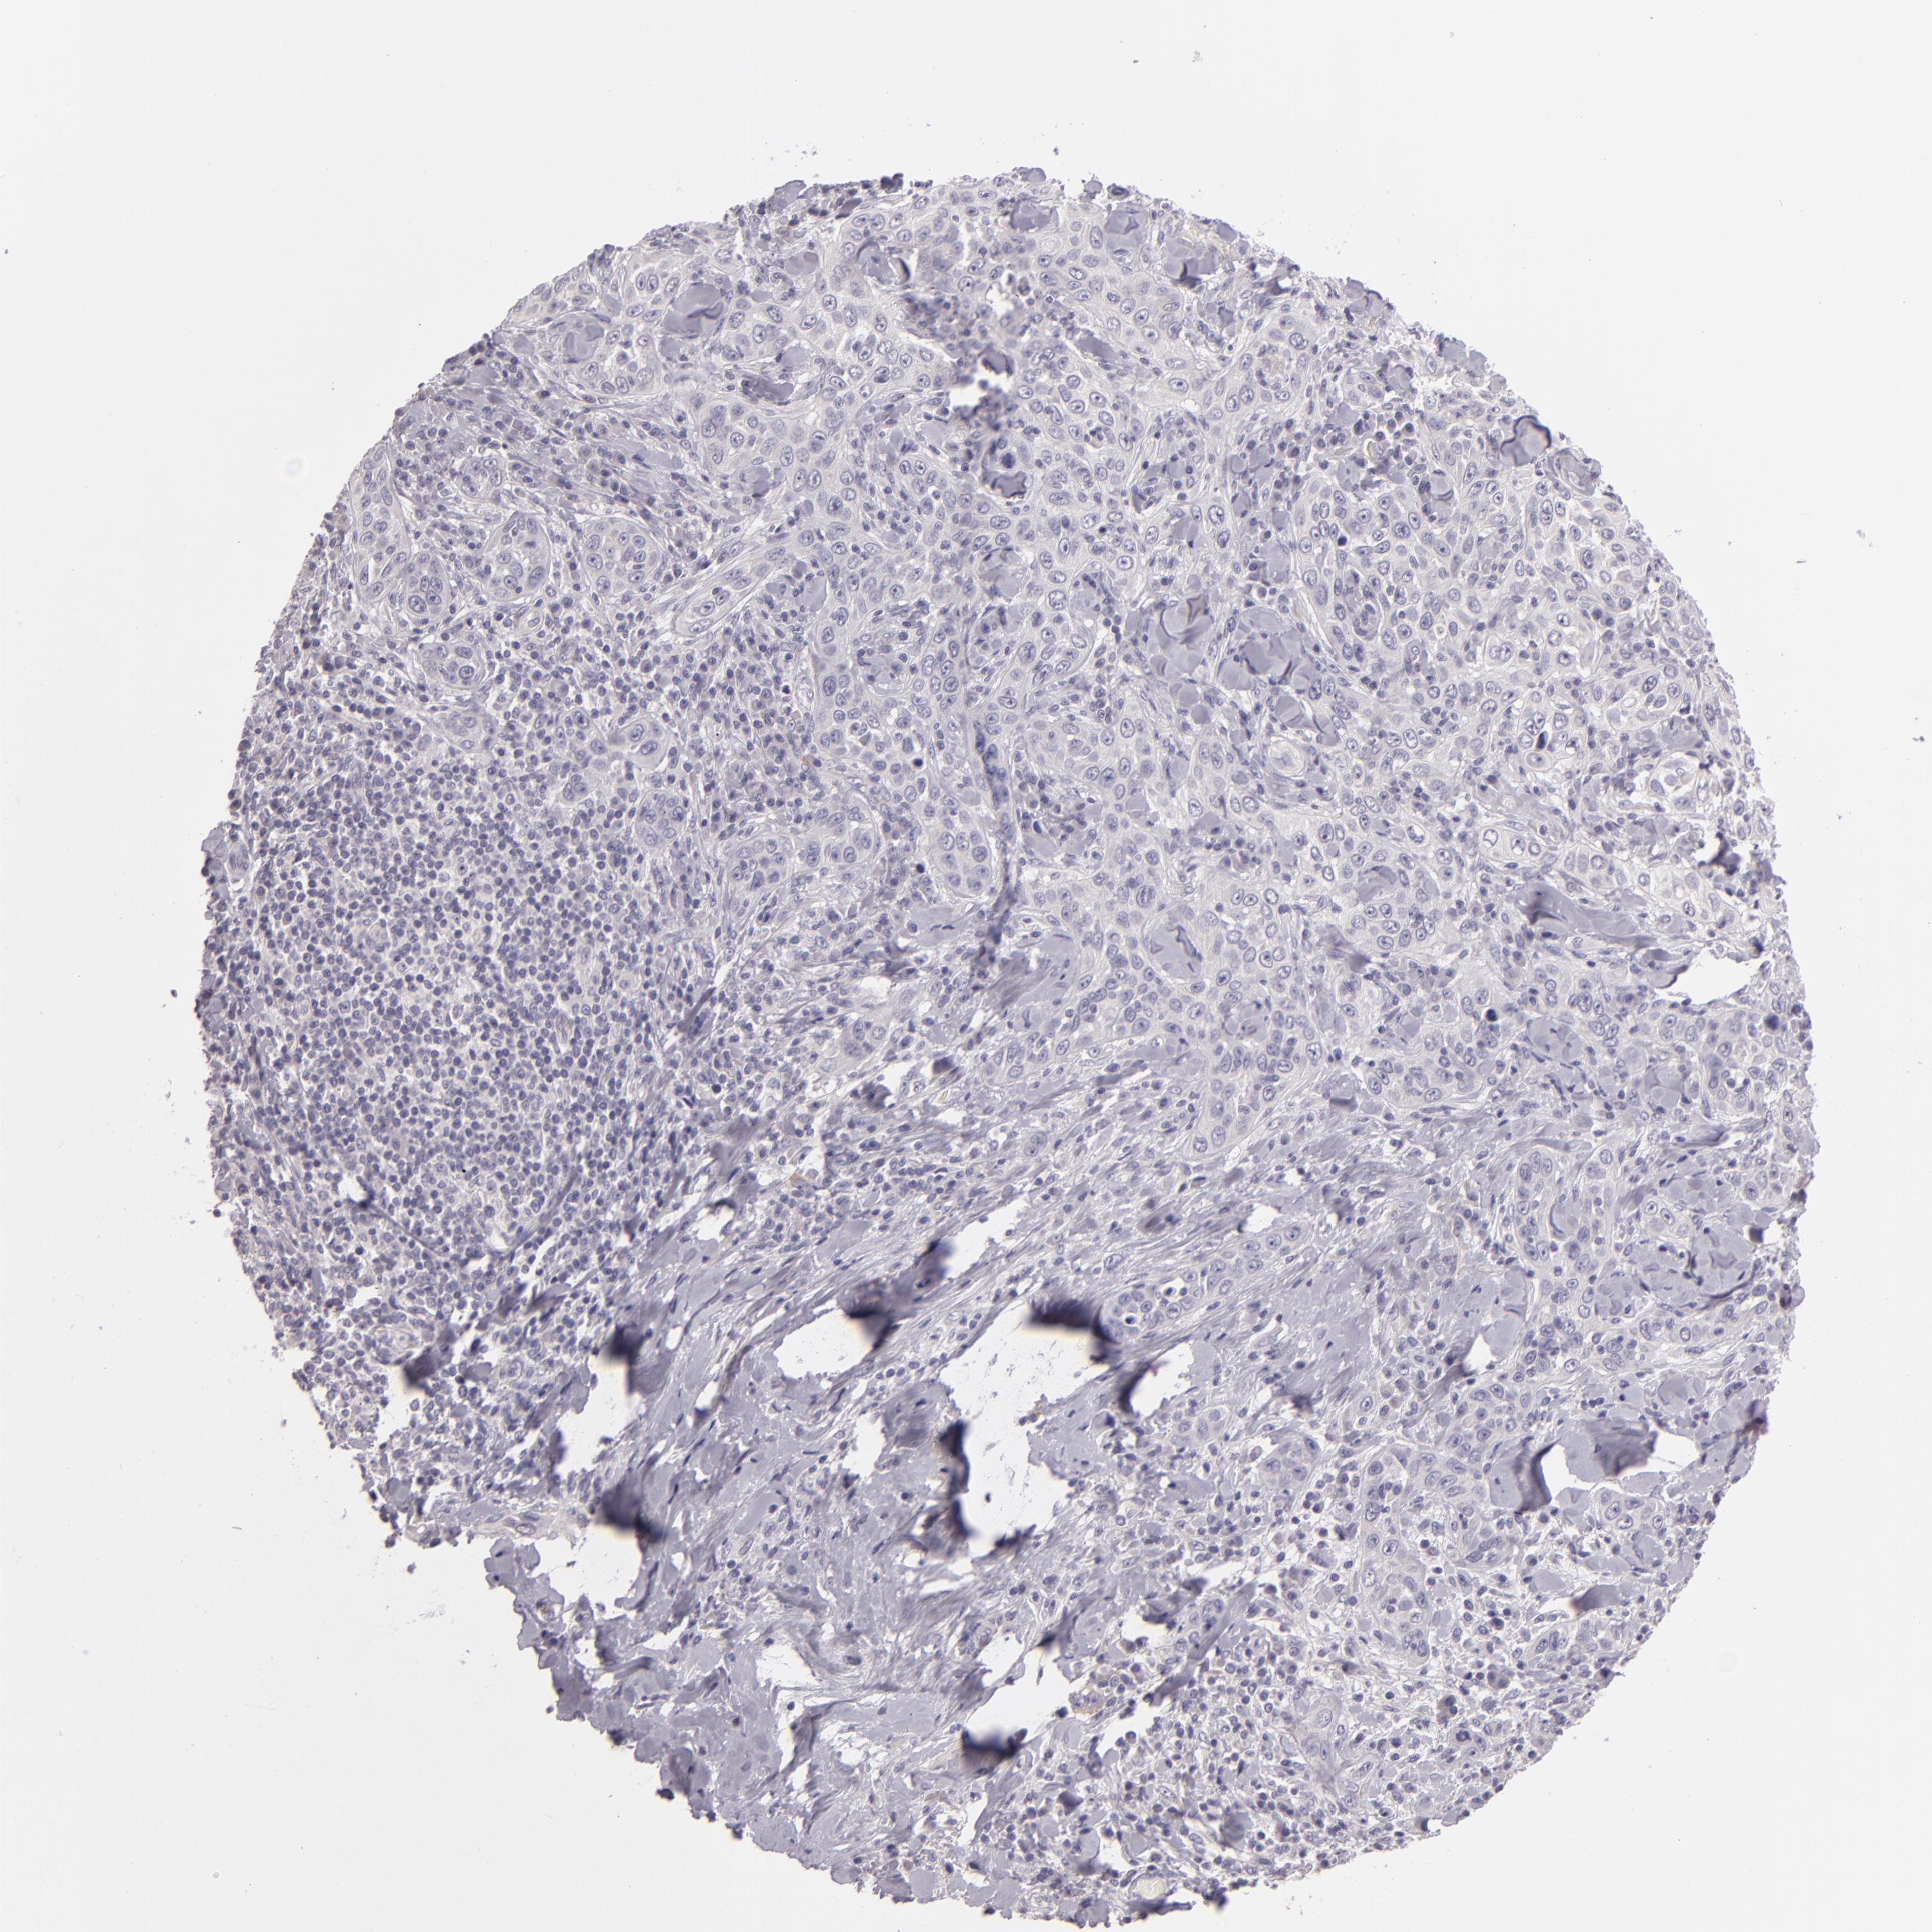

SKIN CANCER - Protein expressioni

A mouse-over function shows sample information and annotation data. Click on an image to view it in a full screen mode. Samples can be filtered based on level of antibody staining by selecting one or several of the following categories: high, medium, low and not detected. The assay and annotation is described here.

Antibody stainingi

Antibody staining in the annotated cell types in the current human tissue is reported as not detected, low, medium, or high, based on conventional immunohistochemistry profiling in selected tissues. This score is based on the combination of the staining intensity and fraction of stained cells.

Each image is clickable and will lead to virtual microscopy that enables deeper exploration of all samples and also displays staining intensity scores, fraction scores and subcellular localization as well as patient and tissue information for each sample.

Antibody HPA001838

Squamous cell carcinoma, NOS

Basal cell carcinoma